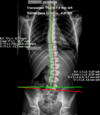

Scoliosis is a deviation of the spine when viewed from the front.

3/A visible curve